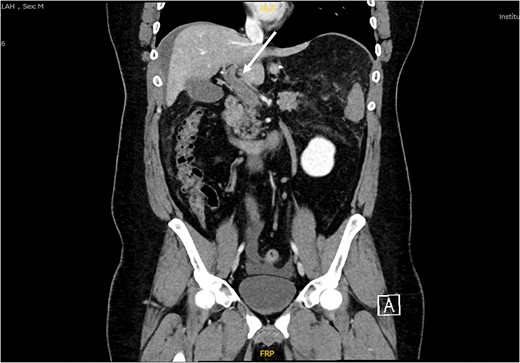

Patient was admitted, and his laboratory investigations demonstrated a normal CBC level, electrolytes were also within normal level, total bilirubin: 17.10 μmol/L, direct bilirubin: 8.80 μmol/L, amino transferase alanine: 36.00 u/L, amino transferase aspartate: 19.00 u/L, alkaline phosphatase: 83 0.00 u/L. Abdomen ultrasound demonstrated mild to moderate intraperitoneal fluid collection, noted mainly in the perihepatic, peri splenic region (Fig. 1). Computed tomography (CT) with oral and IV contrast was ordered for further assessment. The CT showed a non-enhancing portal vein and its branches, a superior mesenteric vein and its tributaries, which are engorged and associated with dirty and congested mesentery, as well as a small amount of peritoneal free fluid denoting venous thrombosis along the portal mesenteric axis with no evidence of contrast leak from the gastric sleeve (Fig. 2). Vascular surgery and hematology consultations were immediately done; they assessed the patient and started him on enoxaparin 100 mg along with a serial abdominal exam. On Day 2 of the current admission, the patient had one episode of fresh blood per rectum, around 150 ml of fresh blood, and dark blood-tinged vomiting of minimal quantity around 10 ml. The patient became agitated, and his abdomen was distended with generalized tenderness. He was immediately resuscitated with two unmatched red blood cell pack transfusions, and then shifted to intensive care units. CT scan angiography of the abdomen was done at that time and reported as follows: non-enhancing portal vein and its branches, superior mesenteric vein and its tributaries, which are engorged and associated with dirty and congested mesentery with a slight increase in the amount of peritoneal free fluid denting venous thrombosis along the portal mesenteric axis. Mild diffuse mural wall thickening of the small bowel is likely related to venous congestion. Aorto-iliac arteries: the visualized abdominal aorta and its bifurcation into right and left common iliac arteries appear intact. The common iliac arteries, internal and external iliac arteries appear intact bilaterally. Mesenteric arteries: the main trunk of the superior mesenteric artery appears intact with no obvious segmental arterial stenosis or occlusion. The inferior mesenteric artery and its main divisions appear intact, with no obvious main or branch occlusion. Celiac artery: The celiac artery and its main divisions, including hepatic, gastric, and splenic divisions, appear intact with no obvious main or branch occlusion.

An ultrasound picture showing free fluid (FF) (white arrow) around the liver (L).

CT scan abdomen and pelvis, coronal view showing non enhancement of portal vein and its branches indicating venous thrombosis along the portal mesenteric axis (white arrow).